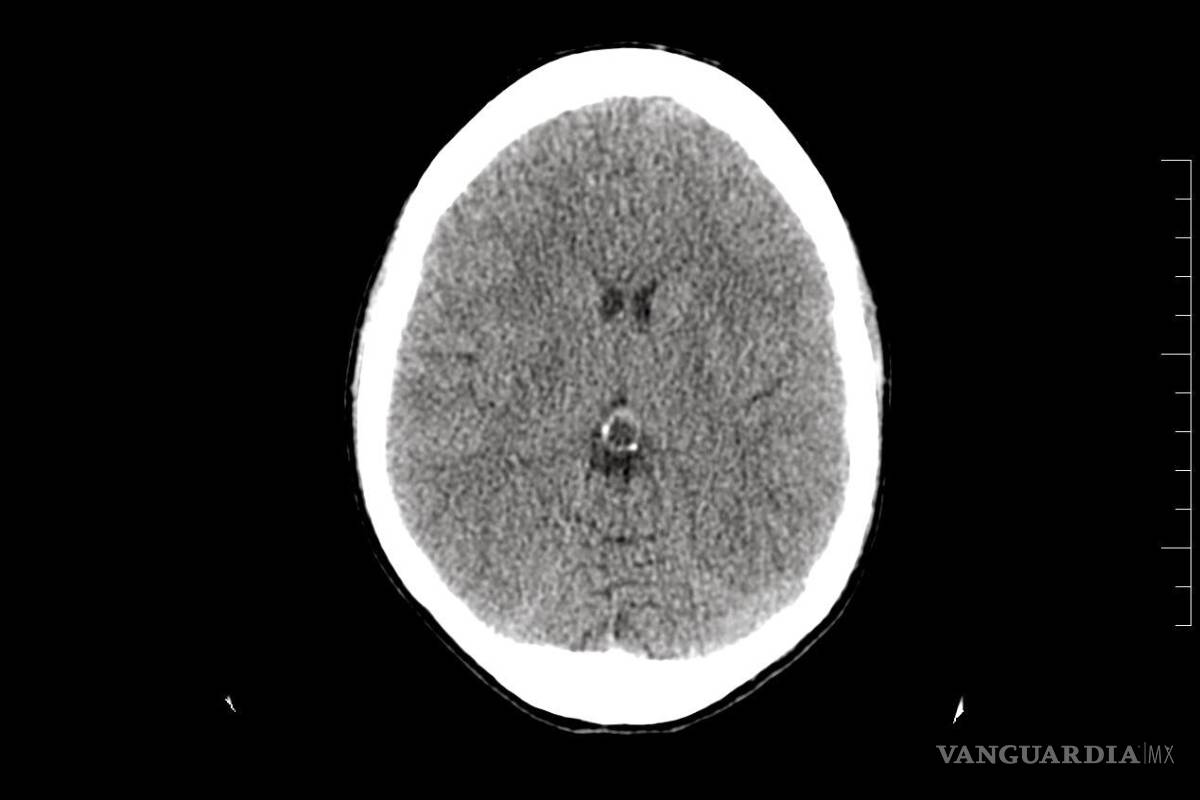

Cuando por fin le hicieron los estudios, éstos revelaron un pequeño tumor benigno en la glándula pineal, pero los doctores aseguraron que no tenía relación con su dolencia. Poco después lo regresaron al hospital debido al incremento de dolor en la cabeza acompañada de vómito. Como no podían operar el tumor lo sometieron a una punción lumbar.